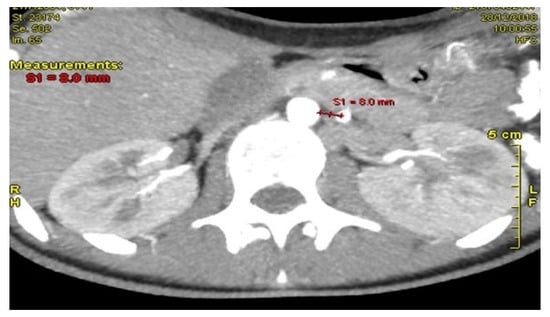

Persistent Vomiting and Epigastric Pain in an Adolescent: A Case of Superior Mesenteric Artery Syndrome Unmasked

Background and Clinical Significance: Superior mesenteric artery syndrome (SMAS) is a rare and often underdiagnosed cause of proximal intestinal obstruction, resulting from compression of the third portion of the duodenum between the SMA and the aorta. It typically occurs in individuals with significant [...] Read more.

Background and Clinical Significance: Superior mesenteric artery syndrome (SMAS) is a rare and often underdiagnosed cause of proximal intestinal obstruction, resulting from compression of the third portion of the duodenum between the SMA and the aorta. It typically occurs in individuals with significant weight loss due to mesenteric fat depletion. CasePresentation: We report the case of a 14.5-year-old female presented with a 6-day history of intractable vomiting and epigastric pain, on a background of intermittent vomiting over the preceding six months associated with a 7 kg unintentional weight loss, culminating in inability to tolerate oral intake. Her clinical course was complicated by a transient episode of blurred vision, numbness, and incoherent speech, initially suspected to be a neurological event. Extensive gastrointestinal and neurological investigations were inconclusive. Elevated fecal calprotectin levels raised suspicion for inflammatory bowel disease, given her family history, though endoscopy and histopathology were unremarkable. Advanced imaging ultimately demonstrated a markedly reduced aortomesenteric angle (6°) and distance (4 mm), confirming the diagnosis of SMAS. The patient was initially managed conservatively with total parenteral nutrition (TPN), achieving partial weight gain of 5 kg after 8 weeks of TPN. Due to persistent duodenal compression, surgical intervention was required. At 7-month follow-up, the patient remained symptom-free with restored nutritional status and a good weight gain. Conclusions: This case highlights the importance of considering SMAS in adolescents with chronic upper gastrointestinal symptoms and significant weight loss. Early recognition and appropriate imaging are essential to diagnosis, and timely surgical management can lead to excellent outcomes when conservative treatment is insufficient. Full article